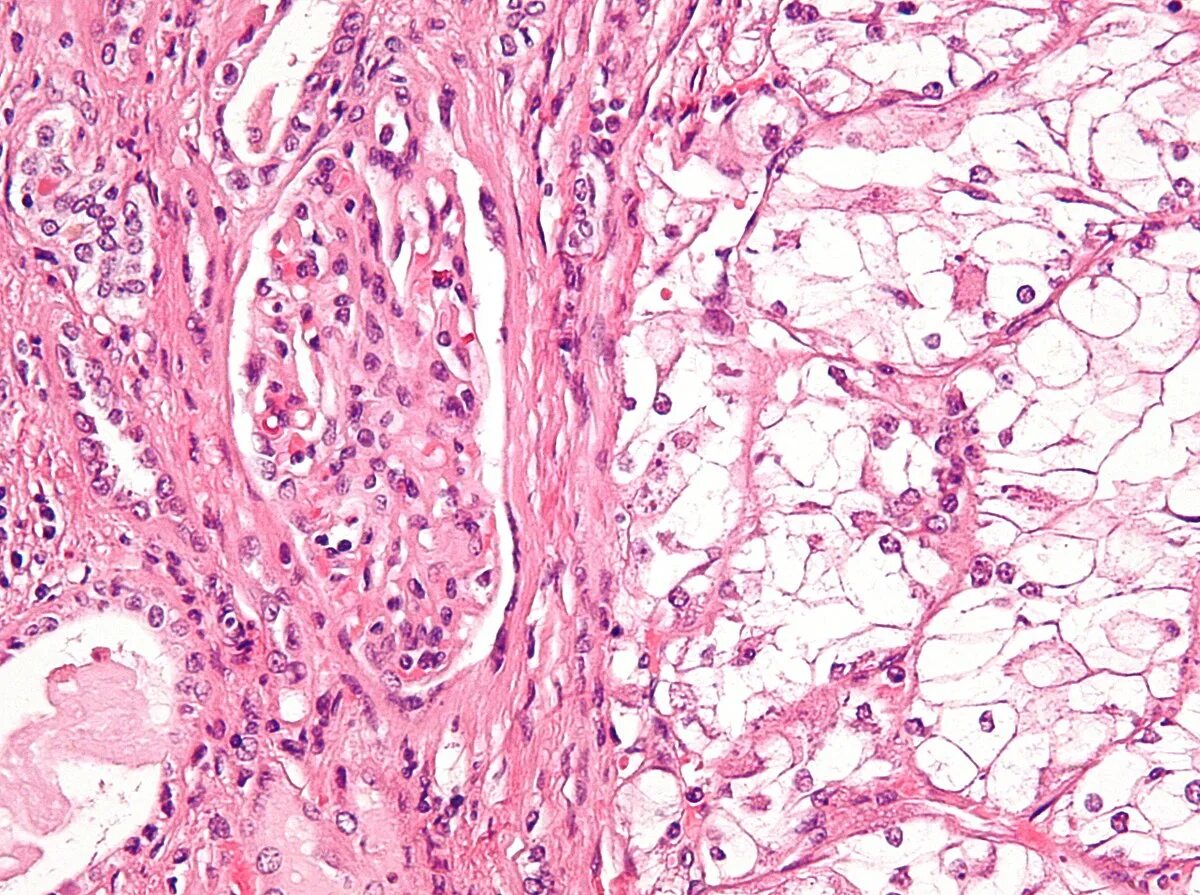

Гистологическое исследование почек